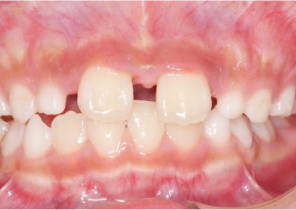

Étude de cas 2

7 ans et 11 mois, 24 étapes d’appareils® d’expansion palatine Invisalign.

Avec l’aimable autorisation du Dr David R. Boschken

Avant le traitement d’expansion avec les appareils d’expansion palatine Invisalign

Après le traitement d’expansion avec les appareils d’expansion palatine Invisalign